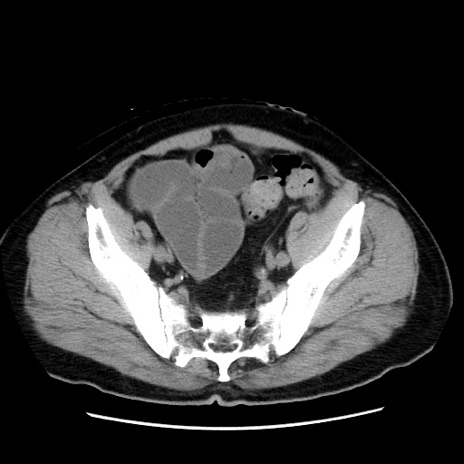

症例16(横断像)

冠状断像

【症例】 70歳代男性

【主訴】 腹痛、嘔吐

【現病歴】 約1ヶ月前より間欠的に腹痛と嘔吐あり、当院消化器内科を受診したところCTで多発する肝臓のLDAを指摘され、精査中であった。以降は消化器症状は安定していたが、2日前より嘔気と腹痛があり、同日より排便・排ガスが消失した。改善認めず、 本日、救急外来を受診した。

【既往歴】 大腸ポリープ切除後。

【身体所見】意識清明・会話良好、BT 36.3℃、BP 127/80mmHg、 P 80bpm、腹部:膨満あり、平坦・軟、上腹部正中および下腹部正中に圧痛あり、反跳痛なし、筋性防御なし。

【データ】WBC 7200、CRP 0.77